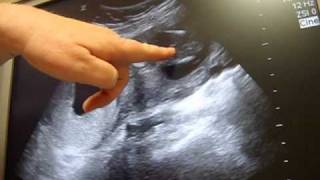

16 weeks gender ultrasound - It's a...